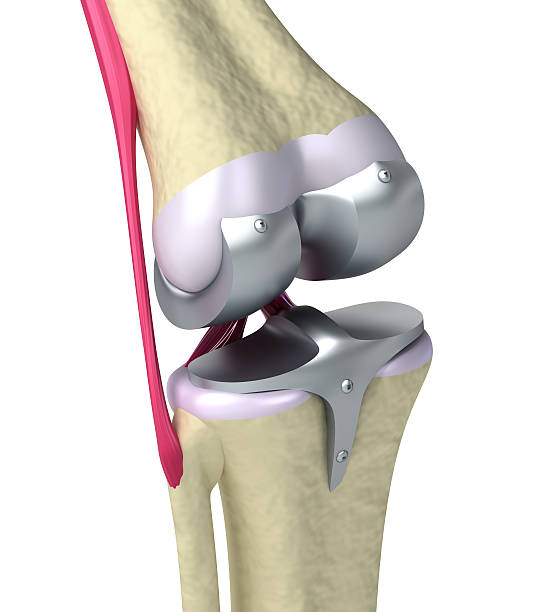

- 대상 질환 : 건강보험급여 '인공관절치환술(슬관절)' 인정기준에 준하는 질환자